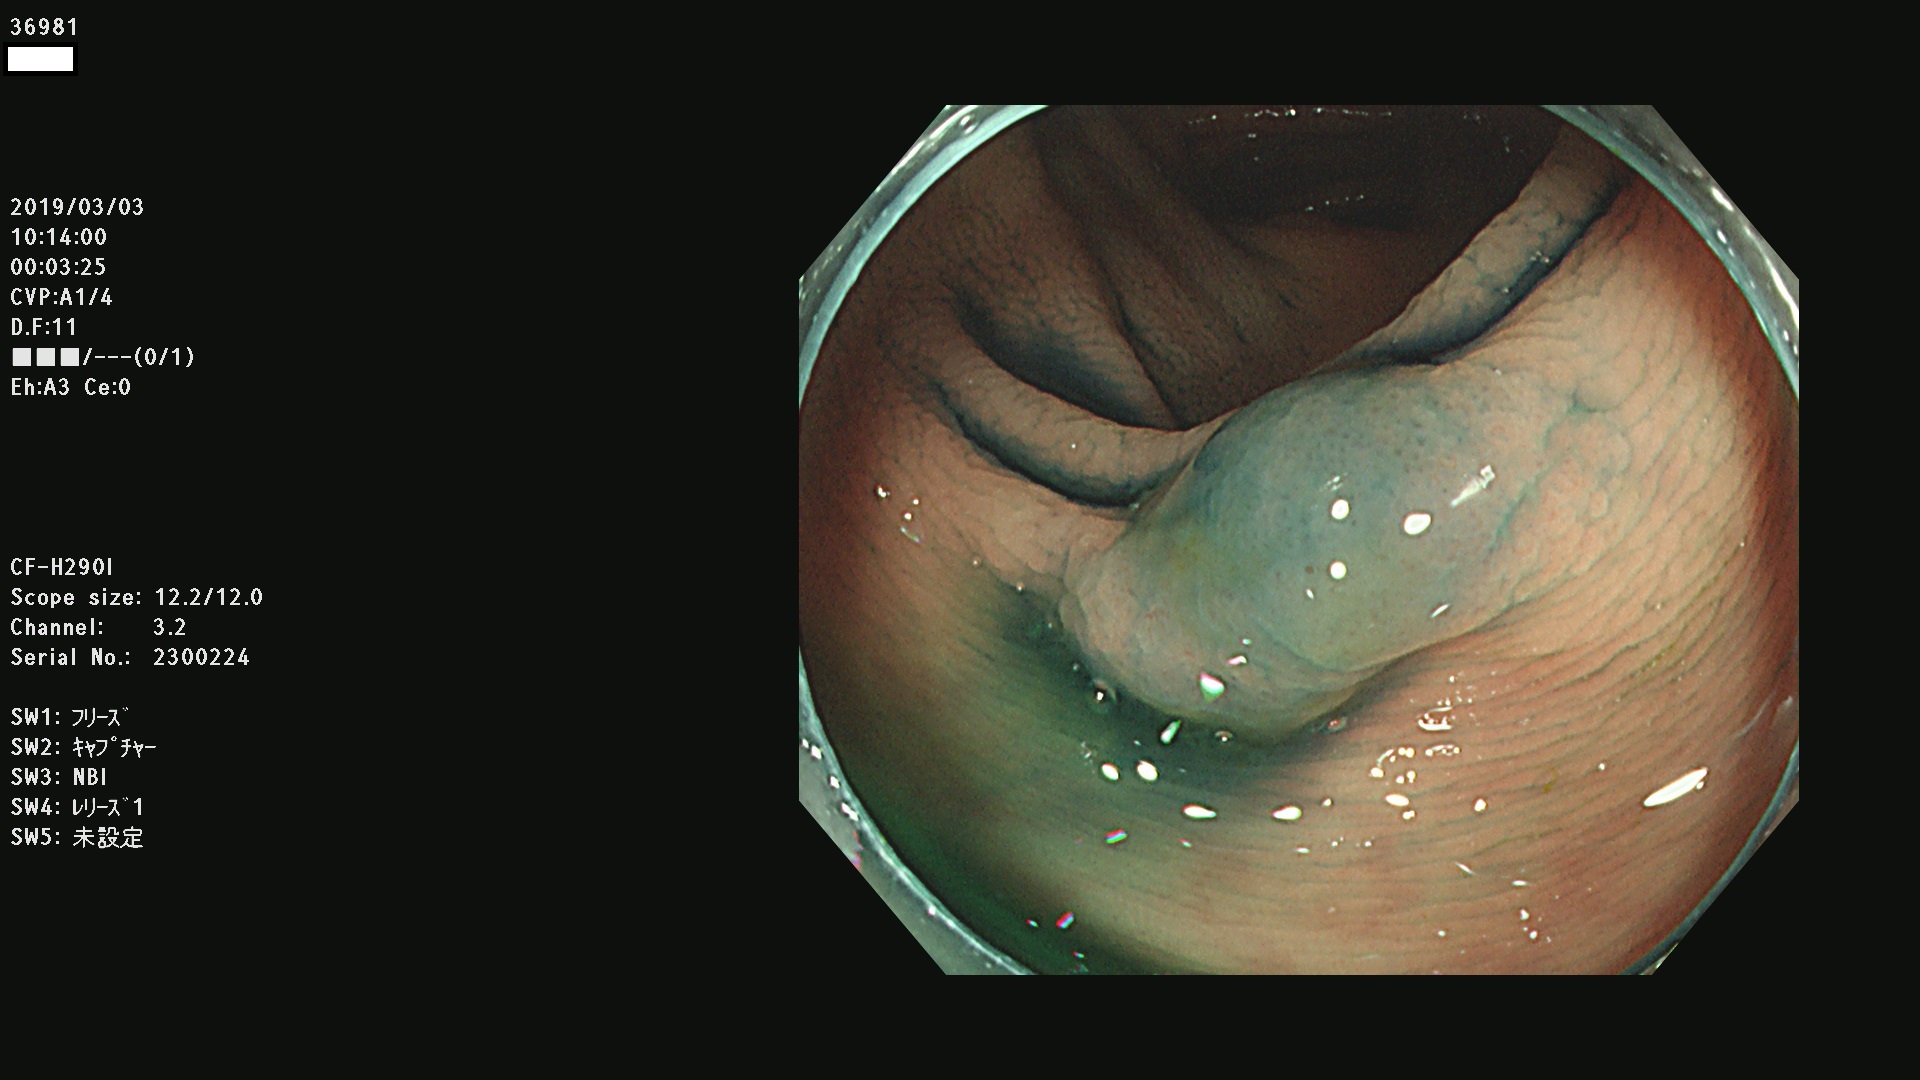

腺腫発見率 67 % (カルテ番号 36900〜36999の100名の方の検査結果で集計)大腸癌検診最新情報

以下のカルテ番号の方に腺腫(Adenoma,Group3〜5)が見つかりました(集計法)

36900 36901 36903 36904 36905 36908 36909 36910 36911 36913 36914 36915 36916 36917 36918 36919 36920 36923 36924 36925 36927 36928 36930 36931(SSAPのみ) 36933 36935 36936 36937 36941 36943 36944 36945 36946 36949 36951 36953 36954 36955 36957 36963 36965 36966 36967 36968 36969 36970 36974 36975 36976 36977 36978 36979 36980 36981 36983 36984 36986 36987 36988 36989 36990 36991 36993 36994 36996 36998 36999

発見困難で危険性の高い平坦型病変(上記100名より抽出) ![]()